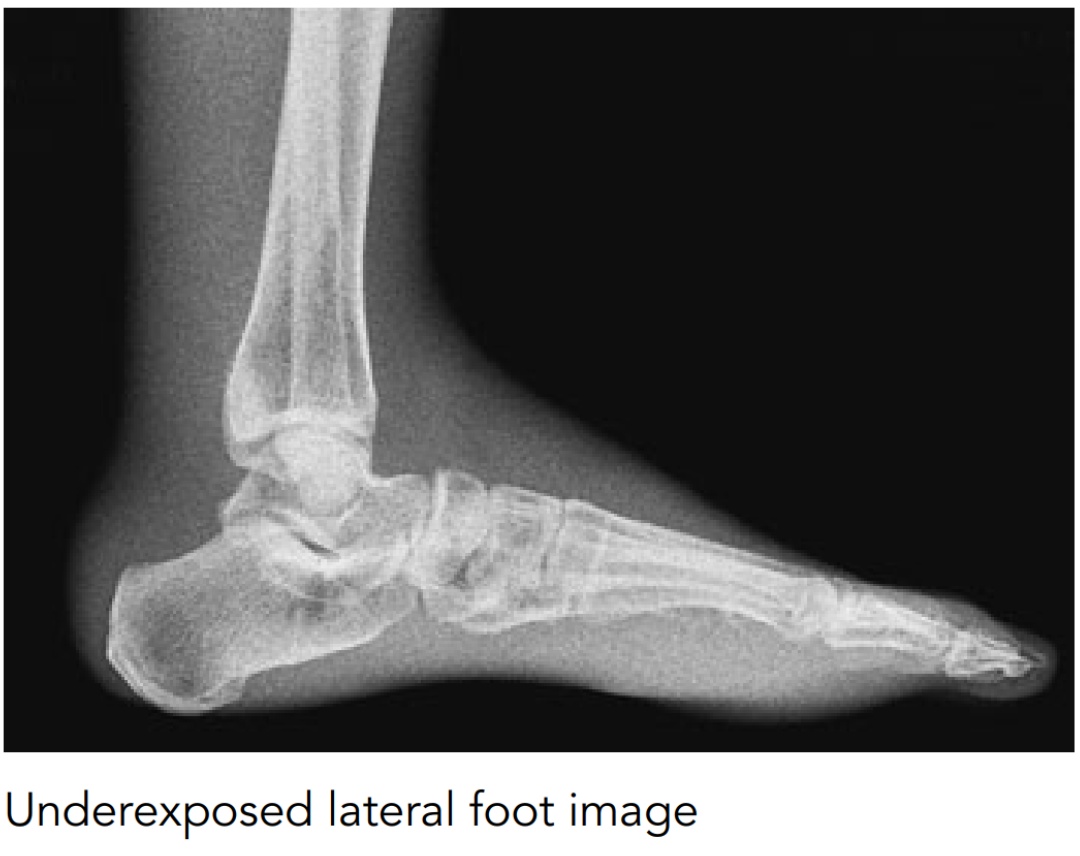

detector. Although a relatively low exposure will result in a noisy image, it may still contain sufficient information to be diagnostically acceptable. A high exposure will result in improved image quality, since quantum noise is reduced. However, image-quality improvement is not linear: it will eventually level off as the quantum noise becomes less dominant and decrease as the plate becomes overexposed. Ideally, a system should be set up to obtain adequate image quality for the lowest possible dose (optimization).